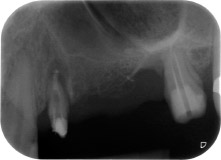

apical periodontal lesion at tooth 24

Fig. 1: 58-year-old patient. Preoperative radiograph showing an apical periodontal lesion at tooth 24 and horizontal loss of alveolar bone in the second quadrant.

Postoperative radiograph

Fig. 16: Postoperative radiograph showing the implants in place, with bone substitute material from the internal sinus lift around the apices. There is some material from the GTR procedure visible around the roots of tooth 24.